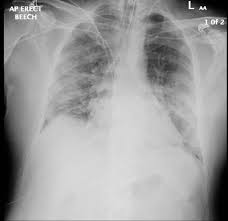

٧- عاصفة السيتوكين ومتلازمة ضيق النفس الحاده

ARDS

٦- في حالة وجود امراض قلب مسبقه قد يحدث ويحفز هذه المشكله بسبب الاشياء التي قد ذكرتها بالاعلى